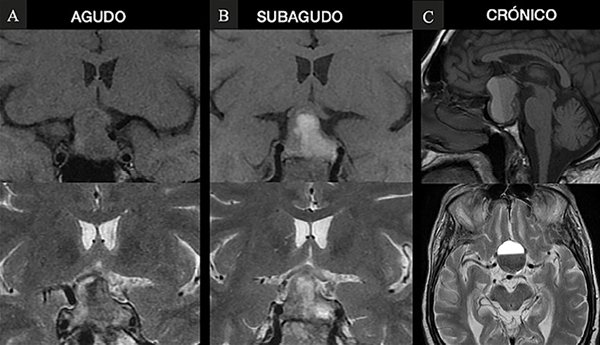

Se analizaron retrospectivamente las historias clínicas de 14 pacientes con diagnóstico de apoplejía hipofisaria intervenidos quirúrgicamente por vía endoscópica endonasal en un periodo de 7 años, comprendido entre enero de 2013 y diciembre de 2019, en dos Servicios de Neurocirugía de la Ciudad de Buenos Aires (uno público y uno privado). El diagnóstico de AH fue definido por un cuadro de cefalea súbita intensa, alteraciones visuales y disfunción adeno-neurohipofisaria, acompañado de estudios por imágenes que demuestren hemorragia/infarto de un tumor hipofisario y diagnóstico anatomopatólogico de adenoma2. Se clasificaron los pacientes según las guías del Reino Unido y el sistema de clasificación de Jho y col.8-9 Todos los pacientes fueron estudiados con tomografía computada (TC) de cerebro y resonancia magnética (RM) de hipófisis sin y con gadolinio y angio RM de vasos intracraneales, analizando las características tumorales, tiempo evolución del sangrado (Figura 1), utilizando la clasificación de Wilson-Hardy y Knosp10,11. Se recabaron los datos endocrinológicos clínicos y el panel hormonal completo pre y postquirúrgico, con dosaje de T4 (tiroxina) libre, TSH (tirotrofina), GH (hormona de crecimiento), IGF1 (factor de crecimiento insulino-símil tipo 1), ACTH (adrenocorticotrofina), cortisol, PRL (prolactina), LH (hormona luteinizante), FSH (hormona foliculoestimulante), estradiol (en mujeres) y testosterona (en varones). El hipopituitarismo fue definido como la deficiencia en al menos 1 de los ejes hipofisarios. Fueron investigados los posibles factores precipitantes de hemorragia. Se analizaron los exámenes oftalmológicos pre y postoperatorios, registrando los resultados del CV y AV de todos los pacientes.

Fig. 1. RM donde se visualizan los distintos estadios de hemorragia. A. Agudo: iso en T1 e hipo en T2. B. Subagudo: hiper T1 e hiper T2. C. Crónico hipo T1 e hipo T2, con nivel líquido.